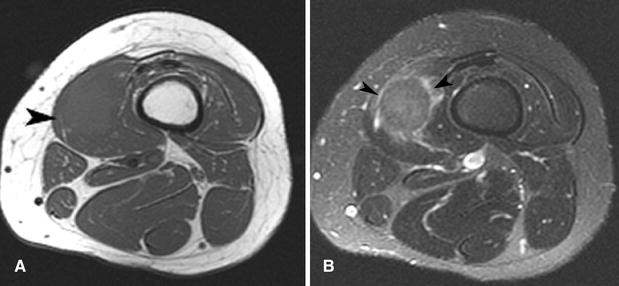

3) Imagen

3.1 Regla práctica

El GCT no tiene un patrón de imagen realmente específico. La utilidad de la imagen depende mucho de la localización y del diferencial local. En mama, por ejemplo, puede simular carcinoma; en tejido blando superficial puede parecer una lesión benigna inespecífica.

3.2 Qué aporta la imagen

- Define tamaño y planos anatómicos.

- Ayuda a planificar resección o biopsia.

- No suele permitir distinguir con seguridad entre benignidad y malignidad.